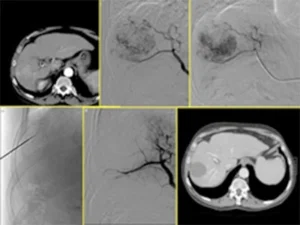

Un altro tipo di tumore del fegato, più raro, è il carcinoma fibrolamellare. Questa forma di cancro è generalmente diagnosticata in pazienti giovani e, rispetto al carcinoma epatocellulare, tende ad essere meno invasiva e a crescere in modo più ben delimitato. Una caratteristica distintiva del carcinoma fibrolamellare è la presenza di una lesione fibrotica centrale, visibile attraverso tecniche di diagnostica per immagini come la risonanza magnetica o la tomografia computerizzata (TC).

Sebbene si tratti di una forma rara, il carcinoma fibrolamellare viene trattato nella maggior parte dei casi come il carcinoma epatocellulare, con approcci terapeutici che possono includere chirurgia, trapianto di fegato, chemioembolizzazione o terapia sistemica.